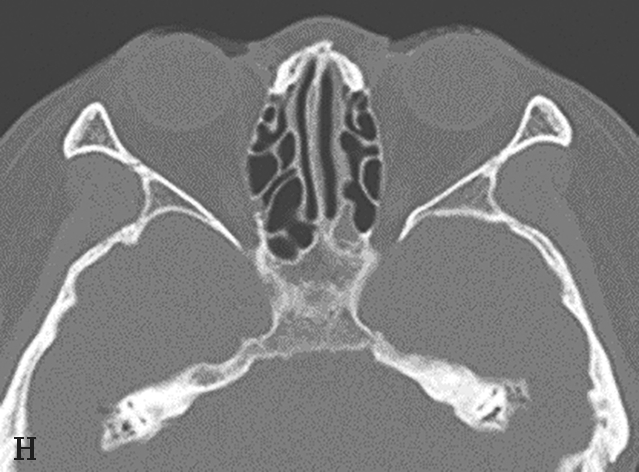

图1-3-7 蝶窦及蝶窦区解剖变异

A.颈内动脉管突入蝶窦;B.蝶窦间隔(白箭);C.左侧翼突气化;D.蝶嵴(星)、蝶骨大翼(白箭)、鞍背气化(虚箭);E.蝶骨小翼气化(白箭);F、G.鞍前型蝶窦(三角);H、I.甲介型蝶窦;J、K.鞍型蝶窦;L.Odoni气房(白箭)